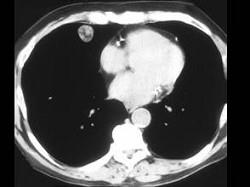

女,71岁,咳嗽,咳痰,胸部隐痛2月余,请结合影像学检查图,选出最可能的诊断 ( )A、结节病B、肺转移瘤C、肺结核D、肺错构瘤E、肺癌

问题 女,71岁,咳嗽,咳痰,胸部隐痛2月余,请结合影像学检查图,选出最可能的诊断 ( )

选项 A、结节病 B、肺转移瘤 C、肺结核 D、肺错构瘤 E、肺癌

答案 D